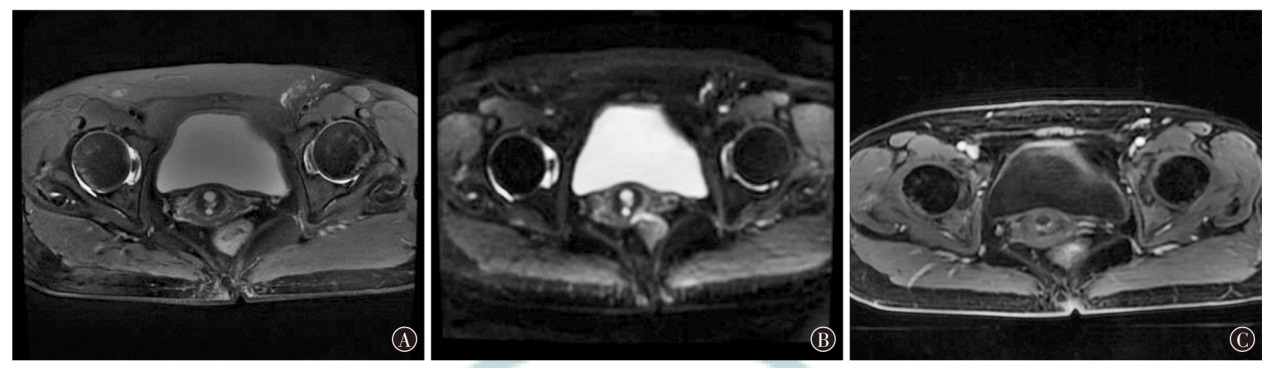

Ishikawa M, Nakayama K, Ishibashi T, et al. Case series of cerebral infarction with trousseau's syndrome associated with malignant gynecological tumors[J]. Mol Clin Oncol, 2016, 5(1): 138-142. DOI: 10.3892/mco.2016.888.